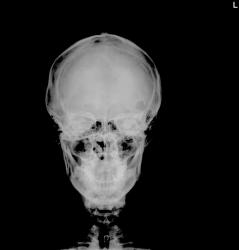

Пациентка, 25 лет. поступила в гинекологию с тупой травмой живота, разрывом кисты яичника. Слева в затылочной кости - зона просветления неправильно овальной формы с четкими контурами, окруженная склеротическим ободком. Травм, трепанаций на черепе не было. Болей нет.

Пациентка, 25 лет. поступила в гинекологию с тупой травмой живота, разрывом кисты яичника. Слева в затылочной кости - зона просветления неправильно овальной формы с четкими контурами, окруженная склеротическим ободком. Травм, трепанаций на черепе не было. Болей нет.

Я бы сделала снимки по Шуллеру и, если это не окажется крупной ячейкой сосцевидного отростка, направила бы на КТ.

по-моему это не ячейка. а что даст КТ? в любом случае, это что-то доброкачествеенное(ободок остеосклероза). в понедельник посмотрю кости таза.

КТ - это на крайний случай. А даст оно очень много: и контуры "дефекта" и локализацию, и мягкотканный компонент и структуру его.

С остеосклерозом Вы по-моему погорячились, здесь всего лишь ровный, подчеркнутый контур, как у лобной пазухи, например. Насчет доброкачественности согласна.

был случай эозинофильной ганулемы. хотя немного другие очаги были. сначала увидели очаги в тазу, потом в бедрах и в черепе.

Nela , сделали по Шюллеру, боковые линенейные томограммы- вроде сливается с ячейками в области верхушки пирамиды. Таз "чистый". написал - крупная ячейка и рекомендовал КТ. завтра представлю р-снимки. странно, но показывали зав. лор отделением - никогда такого не слышала и не видела ... Хотелось бы узнать еще мнение колег из сайта. неужели никому кроме вас не интересно?(((

на счет нижней челюсти - игра света и тени. сам с ней разговаривал - рот очень подвижный), так что норма. просто перед тем как выложить изображения - играл с интенсивностью, для лучшей контрастности находки ( слева в затылочно-височной области, которую вы пометили). что в лобной кости - не обратил внимание, принял за вариант нормы( картины сосудов на черепе такие разные бывают , аж поражаешься ( не утверждаю). завтра выложу еще снимки. если кого задело - не обижайтесь. просто очень хотелось как их то вариантов

В лобной кости просветления за счет неравномерной толщина кости+обработка снимка.

Очень показательные снимки. Крупная ячейка сосцевидного отростка. Кстати пазухи носа также довольно крупные.

Прекрасное наблюдение...спасибо. Касаемо изменений в лобной кости - атипичное расположение ямок Пахионовых грануляций...и всего то...

Здравствуйте, встречали, но редко - на КТ. Бывают частенько варианты дополнительной и продолженной пневматизации костных структур, расположенных рядом с сосцевидным отростком - как вариант развития.

Варианты нормы ... Как часто они заставляют нас "париться".